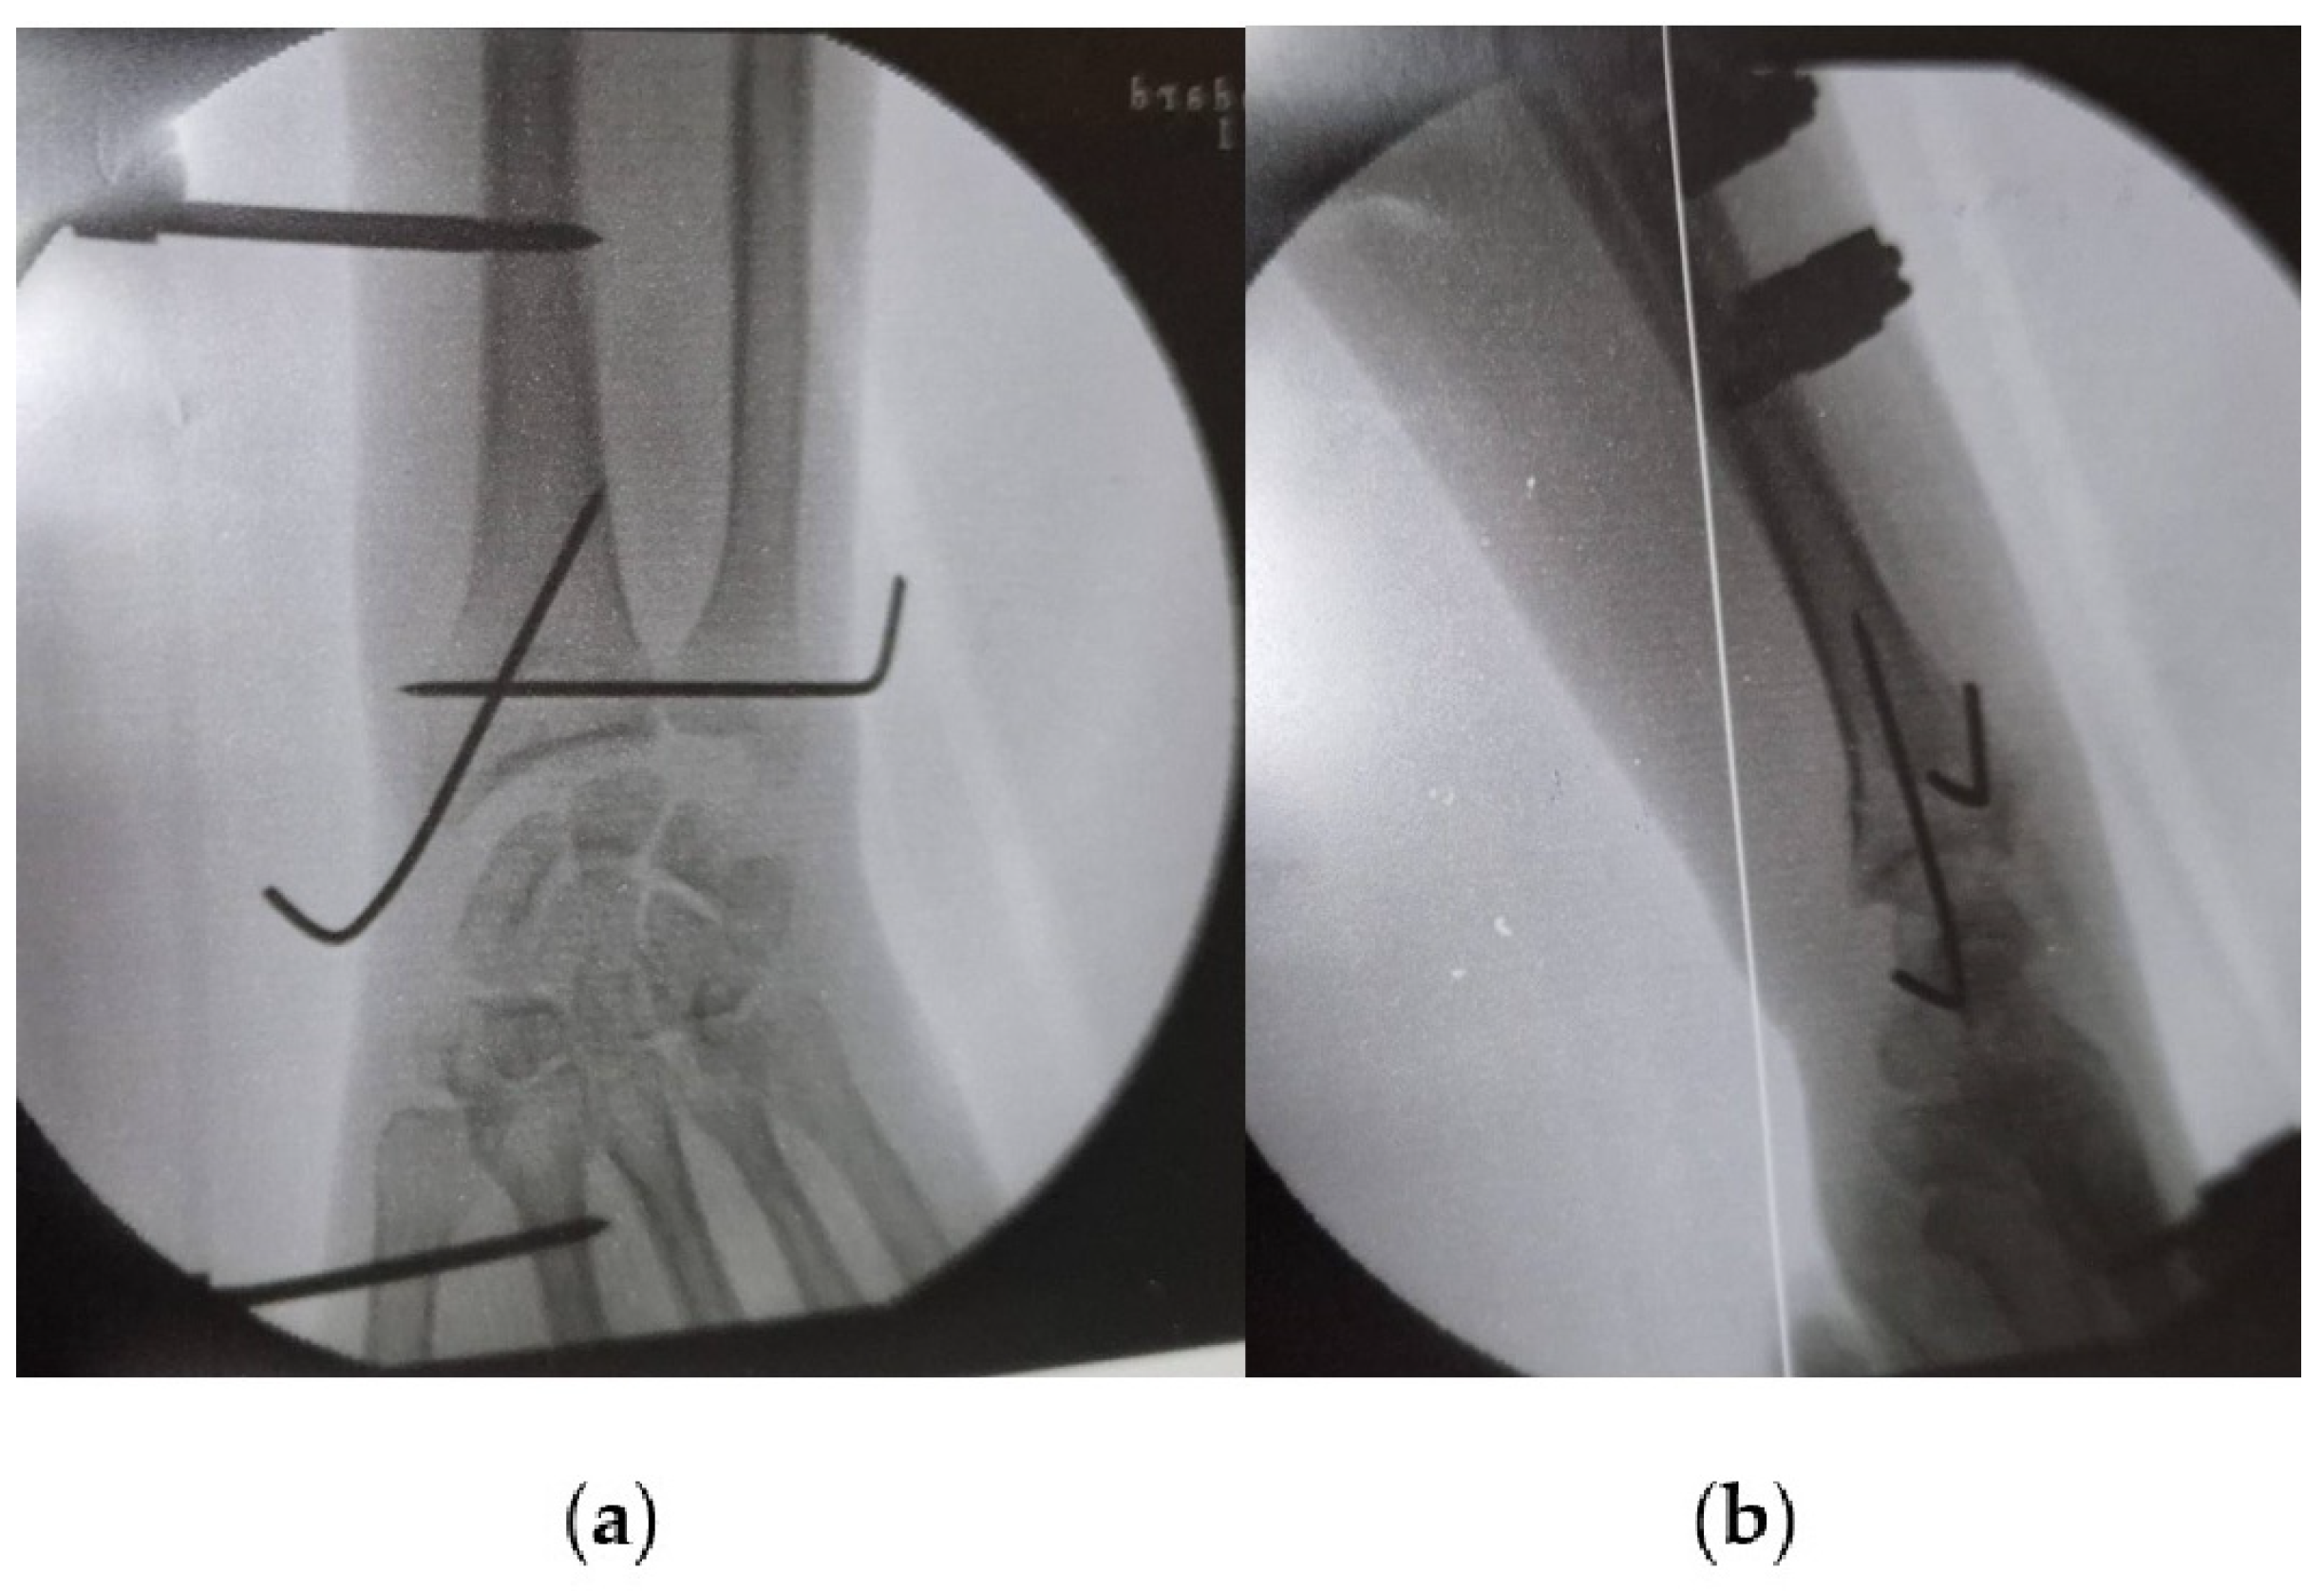

| Isolated DRUJ dislocation | Fall on outstretched hand or direct blow to the wrist | Clinical presentation: dorso-, or volar–ulnar prominence, restricted supination or pronation. Imaging: X-rays, MRI [18,36]. | Closed reduction techniques, immobilization with splint or cast, physical therapy. Surgical options: Kirschner wire insertion, arthroscopic repair of TFCC [18,38]. | Rare; less common than dislocations with fractures [36]. |

| Galeazzi fractures | High-energy trauma | Clinical presentation: forearm swelling, deformity [60]. Imaging: X-rays, CT scans [7]. | Surgical intervention: ORIF, DRUJ stabilization [7,65,66], postoperative care and rehabilitation. Complications may include persistent pain, stiffness, instability [60]. | Comprises approximately 7% of all forearm fractures [61]. |